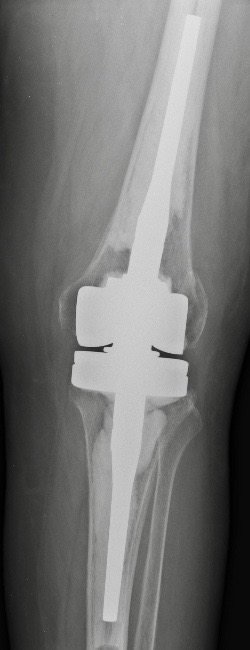

C. PTG de révision

Si faiblesse des ligaments latéraux

Si grandes déformations ou changements de prothèse

quilles d’extension dans le fémur et le tibia pour mieux répartir ces contraintes